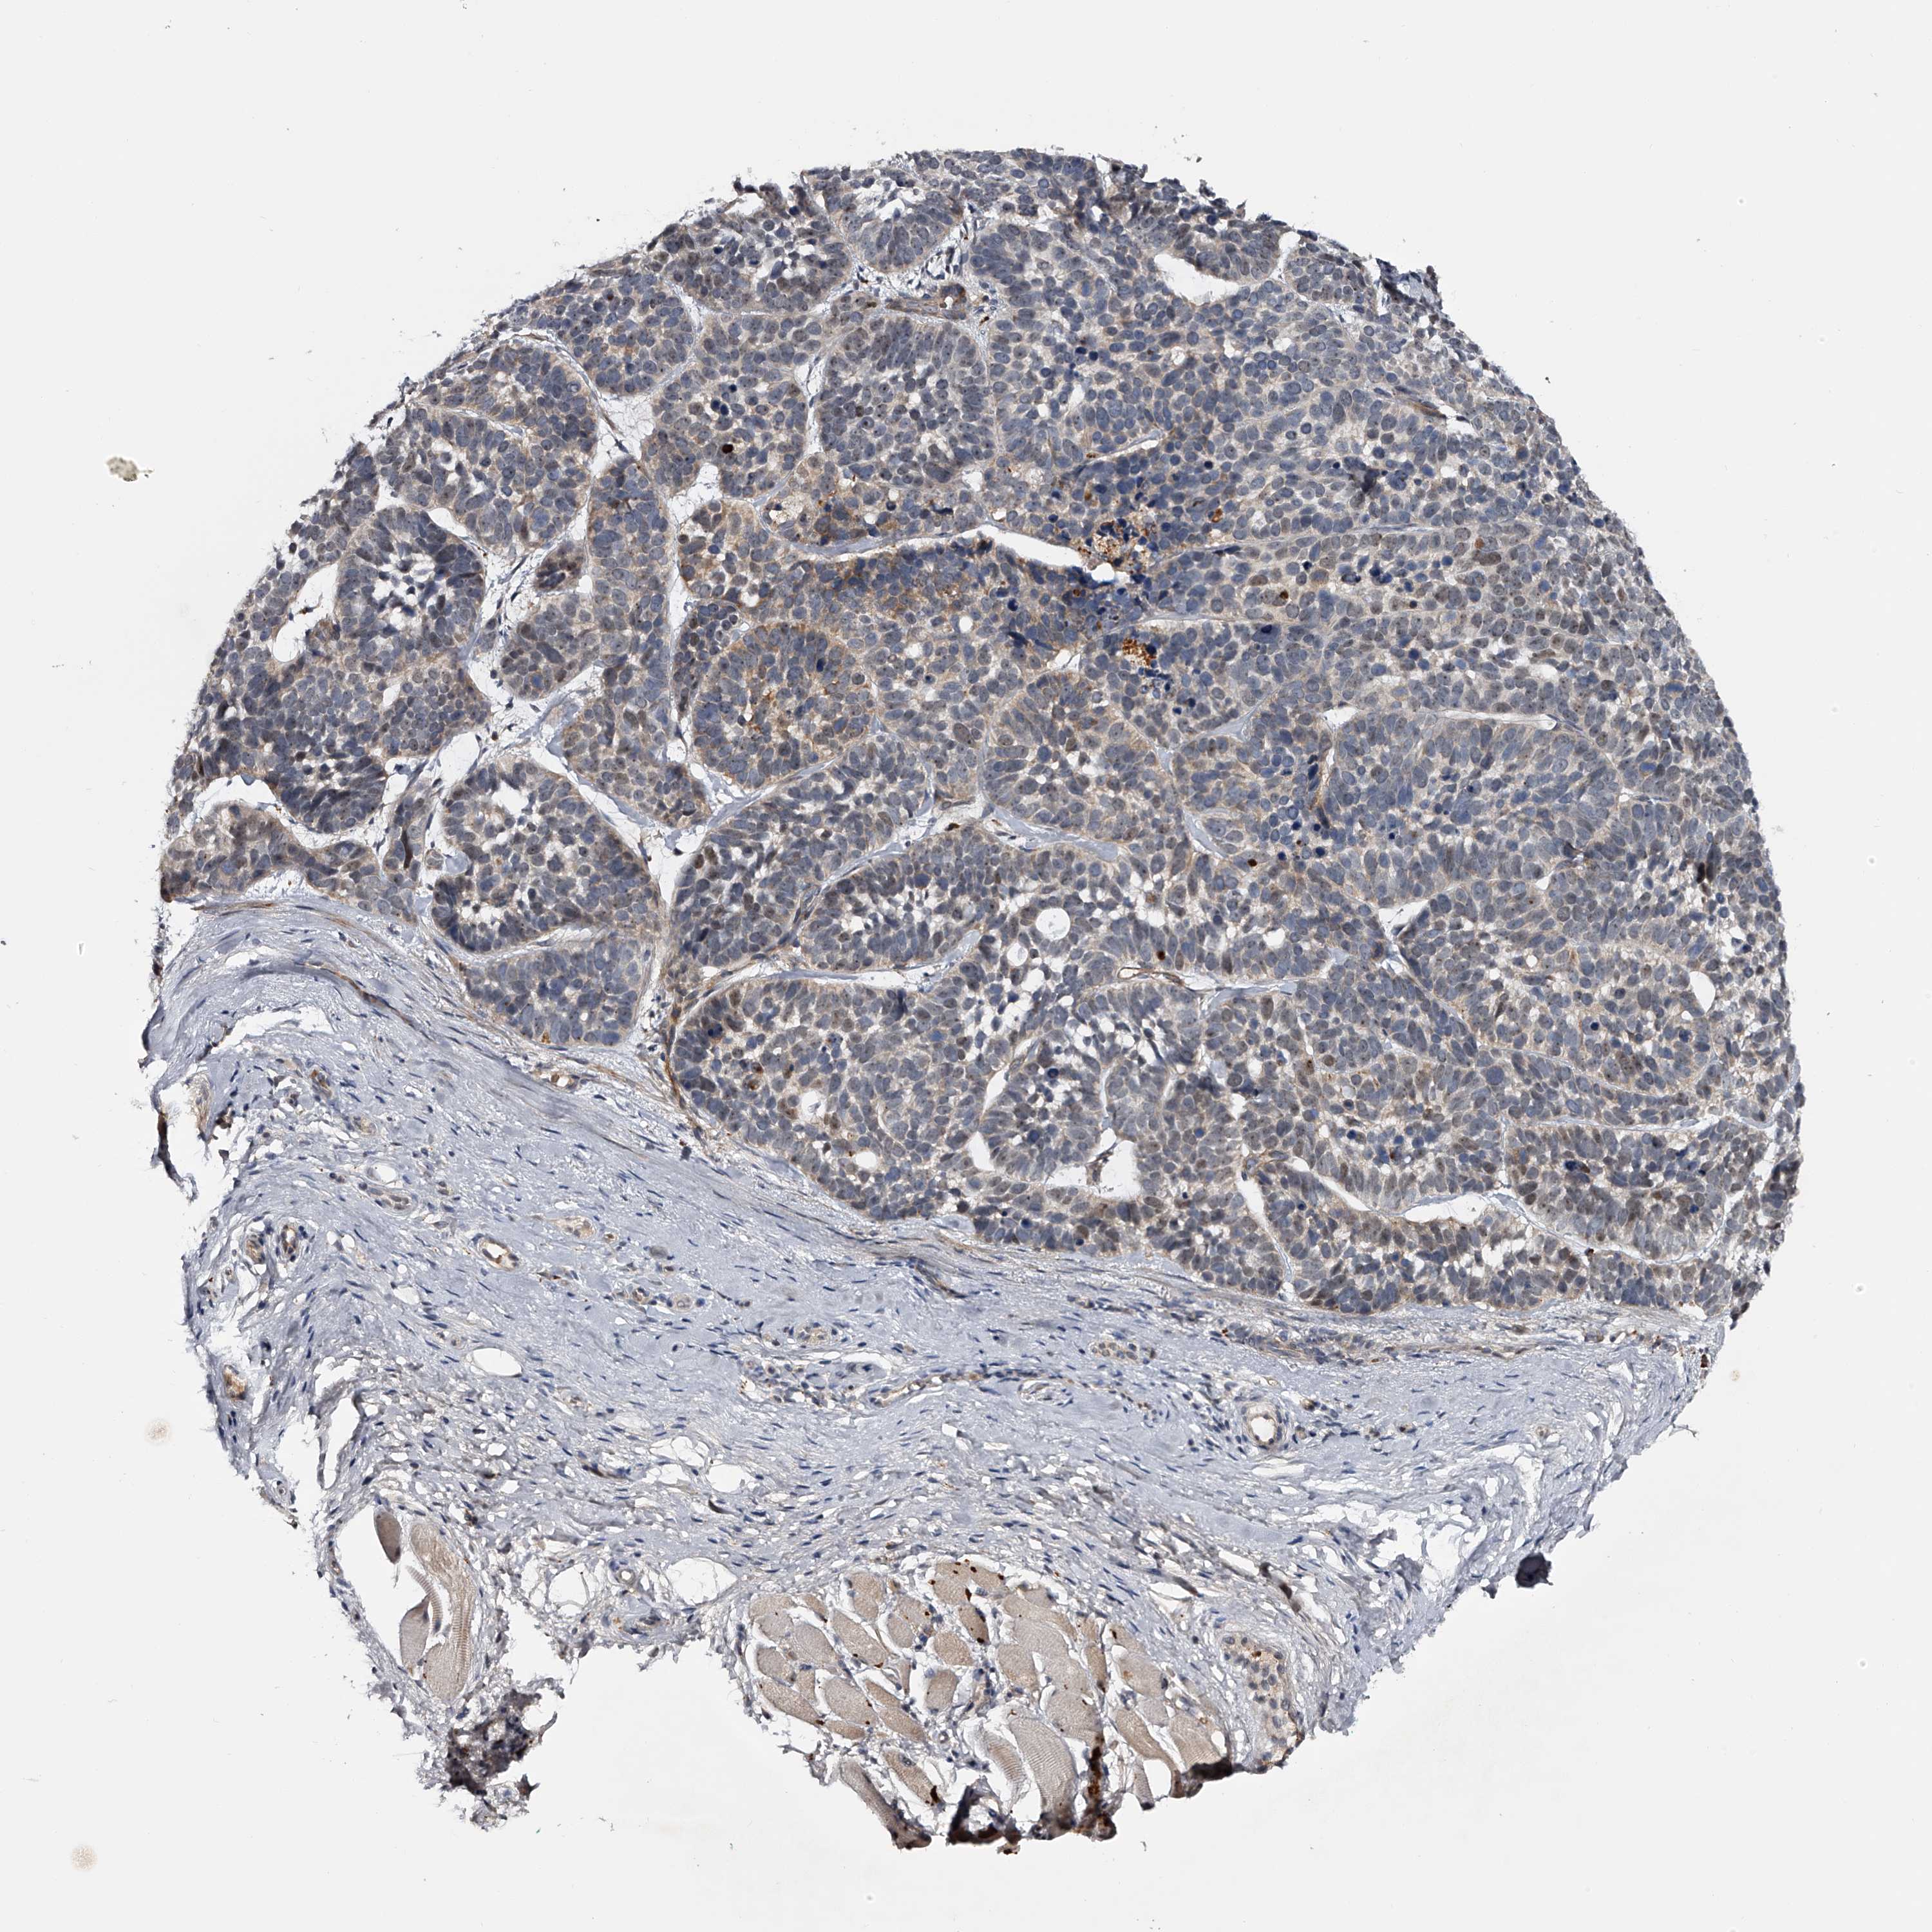

SKIN CANCER - Protein expressioni

A mouse-over function shows sample information and annotation data. Click on an image to view it in a full screen mode. Samples can be filtered based on level of antibody staining by selecting one or several of the following categories: high, medium, low and not detected. The assay and annotation is described here.

Each image is clickable and will lead to virtual microscopy that enables deeper exploration of all samples and also displays staining intensity scores, fraction scores and subcellular localization as well as patient and tissue information for each sample.

Antibody HPA029666

Antibody HPA029667

Antibody HPA029668

Antibody HPA029669

Basal cell carcinoma

Squamous cell carcinoma, NOS

Squamous cell carcinoma, metastatic, NOS